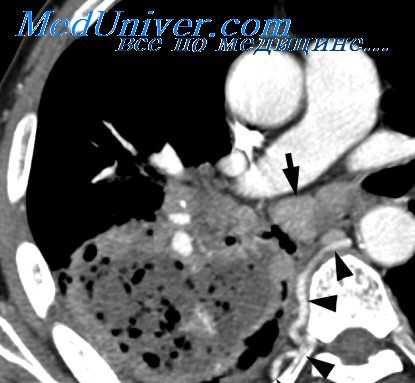

Картина, выявляемая по данным рентгенографии легких, различается в зависимости от формы бактериальной деструкции легких. В типичных случаях легочные деструкции определяются в виде полостей с горизонтальным уровнем жидкости, вокруг которых распространяется воспалительная инфильтрация легочной ткани. При плевральных осложнениях выявляется смещение тени средостения в здоровую сторону, уровень жидкости в плевральной полости, частичный или полный коллапс легкого. В этом случае целесообразно дополнение рентгенологической картины данными УЗИ плевральной полости, плевральной пункции и исследования экссудата. Бактериальную деструкцию легких требуется дифференцировать от полостной формы рака легкого, бронхогенных и эхинококковых кист, кавернозного туберкулеза. В проведении дифдиагностики, должны участвовать пульмонологи, торакальные хирурги, фтизиатры.